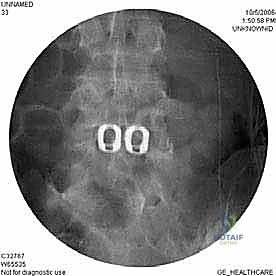

- الأشعة السينية الديناميكية (Dynamic X-rays): صور في وضعيات الانحناء للأمام والخلف لتقييم مدى عدم استقرار العمود الفقري (الانزلاق الفقري - Spondylolisthesis).

- التصوير المقطعي المحوسب (CT Scan): يقدم تفاصيل دقيقة للغاية عن البنية العظمية، وهو ضروري جداً للتخطيط الجراحي، خاصة في حالات استئصال الجسم الفقري أو وجود تعظم شديد.

الخطوة 5: التثبيت (Fixation)

لضمان أقصى درجات الثبات والسماح للعظم بالاندماج بمرور الوقت، يتم تثبيت القفص باستخدام شريحة معدنية صغيرة ومسامير من التيتانيوم تُثبت في الأجسام الفقرية من الأمام. في بعض الحالات، قد يرى الدكتور هطيف ضرورة إضافة تثبيت خلفي بمسامير عبر الجلد (Percutaneous Pedicle Screws) لزيادة الدعم.

الخطوة 6: الإغلاق

بعد التأكد من وضعية الغرسات باستخدام الأشعة السينية داخل غرفة العمليات، يتم إعادة الأوعية الدموية والأعضاء الداخلية إلى وضعها الطبيعي، وتُغلق طبقات البطن بخيوط تجميلية.